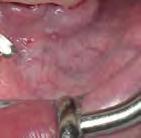

Para los autores Márcio Fernando de Moraes Grisi y Daniela Correa Grisi, las cirugías y técnicas mínimamente invasivas deben ser tomadas como procedimientos de rutina, ya que producen menos molestias, menos complicaciones posquirúrgicas y un máximo bienestar del paciente. No obstante, los doctores Moraes Grisi y Correa Grisi han querido desmitificar la idea de que la realización de los procedimientos mínimamente invasivos solo pueden hacerse con el uso de equipos extremadamente sofisticados.

Ante estas premisas, los autores idearon un atlas dedicado específicamente a los procedimientos periodontales mínimamente invasivos. A lo largo de sus 22 capítulos encontramos desde cómo trabajar con lupas prismáticas, microscopios y todo tipo de instrumental, hasta la presentación del paso a paso de las diferentes técnicas no quirúrgicas y quirúrgicas mínimamente invasivas. Los autores han buscado en cada técnica su comparativa con las técnicas convencionales, apoyándose siempre en las evidencias científicas más recientes.